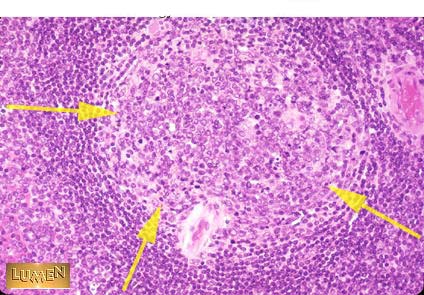

Germinal center

Centroblasts,

Centrocytes,

T helper cells,

Folicular Dendritic cells,

Macrophages